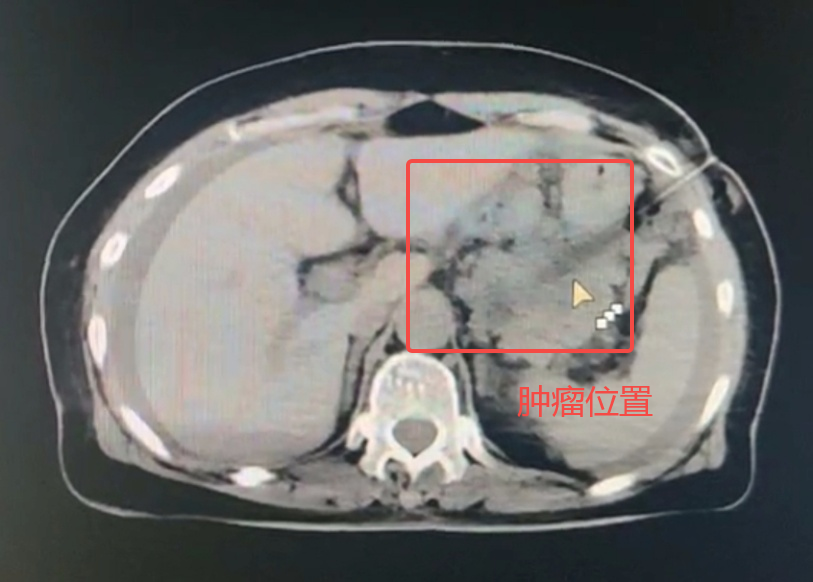

近日,泰康同济(武汉)医院(简称“泰康同济”)肿瘤科戈伟主任团队通过CT引导下胰腺穿刺活检技术,为一名72岁的胰腺肿瘤患者明确诊疗方向,避免了不必要的手术风险和创伤。作为穿刺活检界的技术天花板,这一微创技术是我国每年12万例胰腺癌新患者获得精准治疗的保障。

今年3月份,72岁的蔡奶奶因持续腹胀到某医院就诊,影像检查显示胰腺体尾部肿瘤性病变。4月2日,蔡奶奶转入泰康同济接受进一步检查与治疗。

为明确诊断,肿瘤科戈伟主任团队果断施行CT引导下胰腺穿刺活检,采用“双角度进针法”,先经胃壁建立安全通道,再以18G活检针快速获取3条组织标本,全程仅15分钟。穿刺后仅3天即获得病理报告,结果确诊为胰腺癌,团队随即采取针对性治疗。